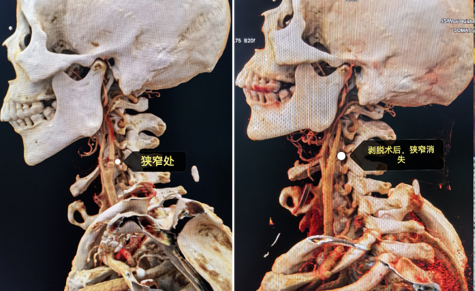

显微颈动脉内膜剥脱术